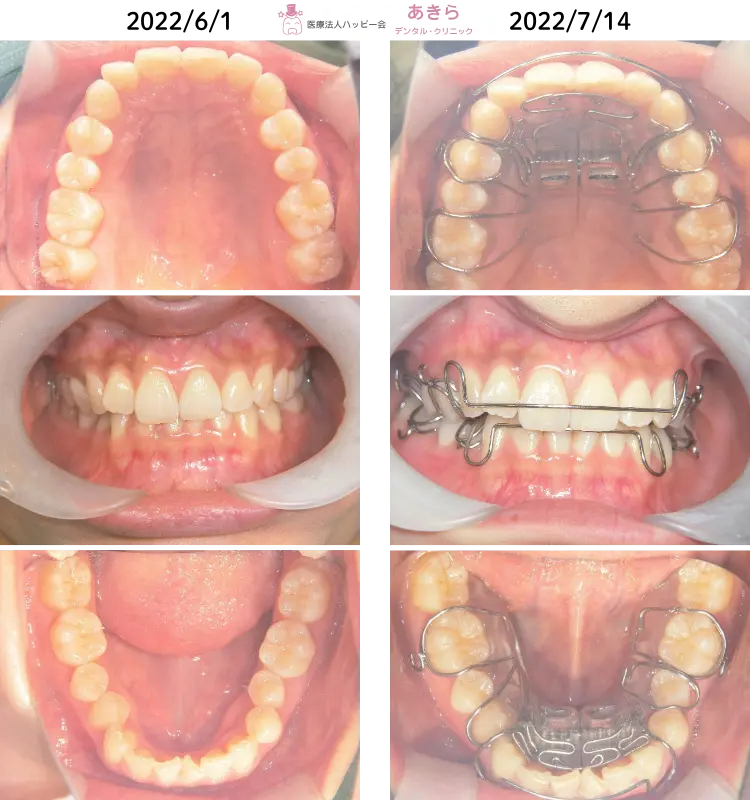

2022年 6月1日 初診時 ⇒ 7月14日 SHAスタート時

- 2022年 7月より「SHA=SH装置」SH療法スタート。

- 上下顎狭窄歯列の解除を主に設計~スタートしました。歯列が直立してくることにより、早期接触がおこりますので、随時必要枠での咬合調整が必要になります。2級ゴム併用しております。